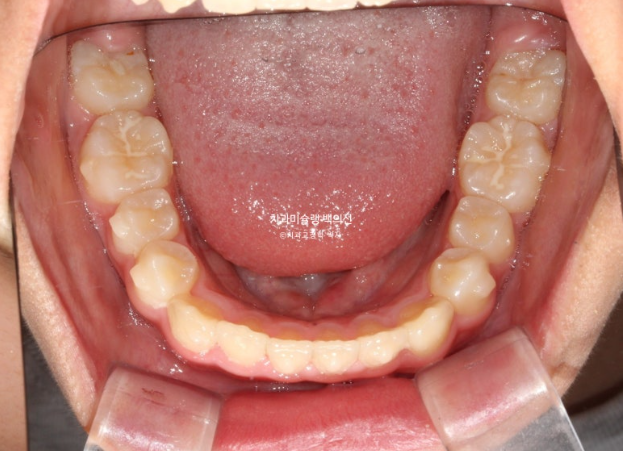

24.02

악궁확장을 통한 덧니 배열을 목표로 인비절라인 퍼스트 교정치료를 권유드렸습니다.

24년 2월부터 9월까지 첫세트의 19개 장치를 모두 낀 후 모습입니다.

24.09

중심선은 개선되었으나 약간의 불일치가 남아있으며 반대교합과 덧니는 모두 개선되었습니다.

그 사이 하나 남아있던 유치가 빠지고 완전한 영구치열에 접어들었습니다.

중심선 개선을 위해 추가장치 제작을 하기로 합니다.